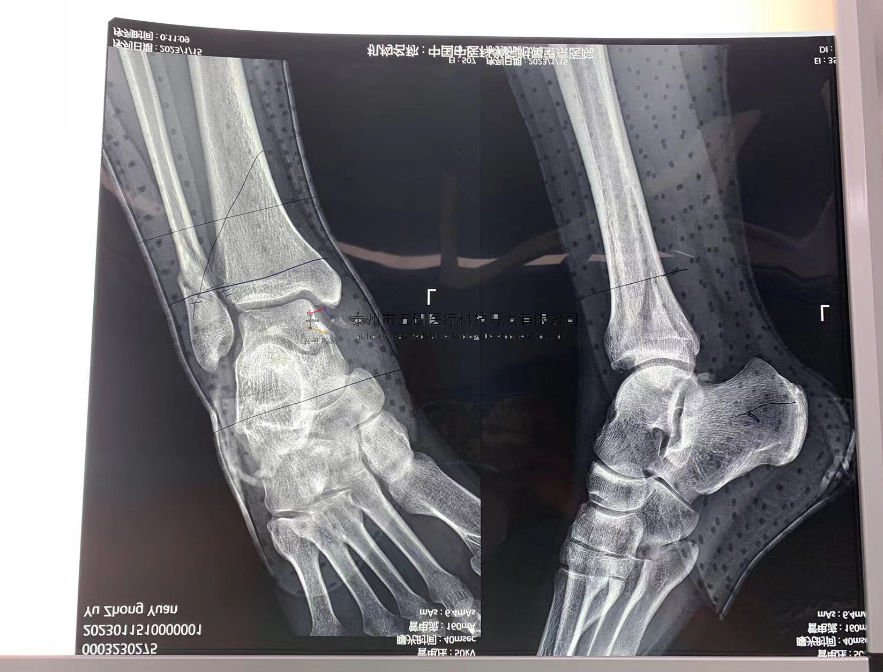

// 腕架

本病例由中國(guó)中醫(yī)科學(xué)院望京醫(yī)院骨綜科提供(術(shù)者:支架醫(yī)生常醫(yī)師)

【基本資料】患者,女,61歲

本病例腕架骨折。術(shù)前正側(cè)位片:右橈骨遠(yuǎn)端骨折。